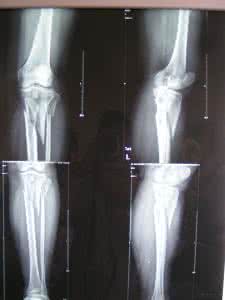

X 线片检查有助于骨折和骨折类型的诊断。

伤后局部疼痛,迅速肿胀,小腿不敢负重,即可拟诊为小腿骨折。若见有成角畸形或骨摩擦征及假活动,则可肯定诊断。根据临床表现和相关检查,不难得出诊断。